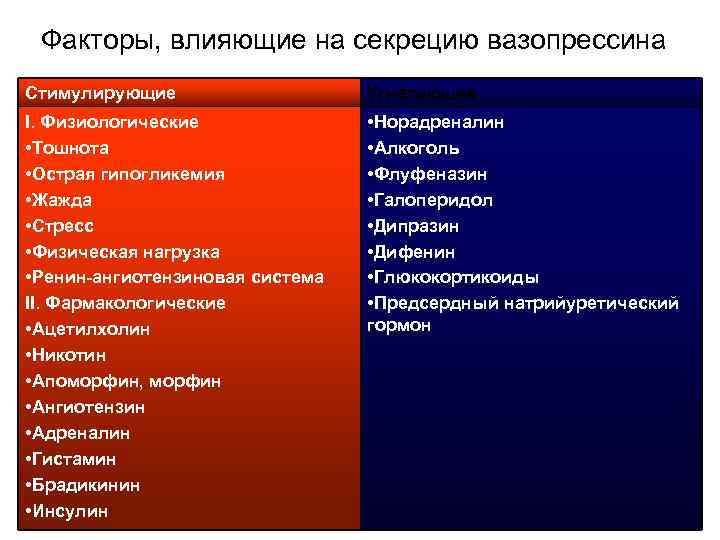

Факторы, влияющие на секрецию вазопрессина Стимулирующие Угнетающие I. Физиологические • Тошнота • Острая гипогликемия • Жажда • Стресс • Физическая нагрузка • Ренин-ангиотензиновая система II. Фармакологические • Ацетилхолин • Никотин • Апоморфин, морфин • Ангиотензин • Адреналин • Гистамин • Брадикинин • Инсулин • Норадреналин • Алкоголь • Флуфеназин • Галоперидол • Дипразин • Дифенин • Глюкокортикоиды • Предсердный натрийуретический гормон

Факторы, влияющие на секрецию вазопрессина Стимулирующие Угнетающие I. Физиологические • Тошнота • Острая гипогликемия • Жажда • Стресс • Физическая нагрузка • Ренин-ангиотензиновая система II. Фармакологические • Ацетилхолин • Никотин • Апоморфин, морфин • Ангиотензин • Адреналин • Гистамин • Брадикинин • Инсулин • Норадреналин • Алкоголь • Флуфеназин • Галоперидол • Дипразин • Дифенин • Глюкокортикоиды • Предсердный натрийуретический гормон